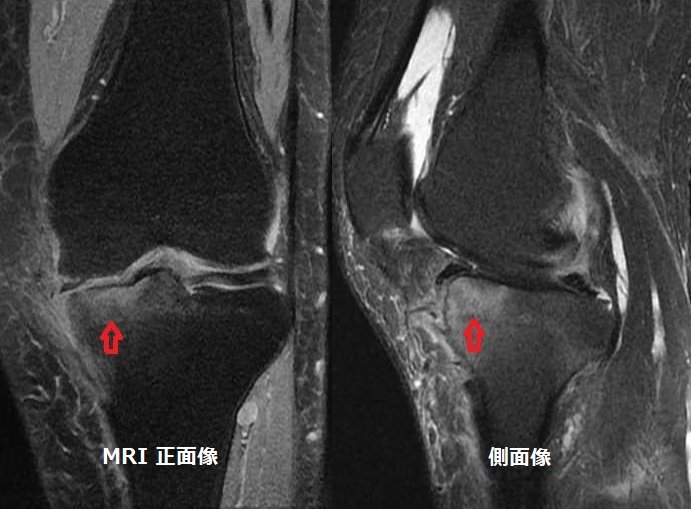

膝関節MRIでみられる骨髄浮腫 (bone marrow edema:BME)は、痛みの強さを表します。

手術前のMRI正面・側面像で赤矢印がBMEです。